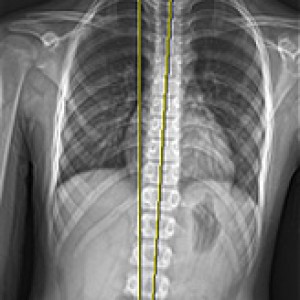

검사부터 다른 당당

“당당은 뼈만 보지 않습니다.”

근육과 근막의 정렬을 함께 진단하며, 풀 스파인 촬영을 통해 머리부터 모든 고관절, 발의 정렬까지 함께 파악하여 개개인에 맞는 전신 치료법을 설계합니다.

전신 엑스레이 검사

다리길이 엑스레이 검사

해당 사진은 수정없는 실제 치료사진입니다.

환자의 치료결과는 환자의 상태, 치료방법 등에 따라 차이가 발생할 수 있습니다.